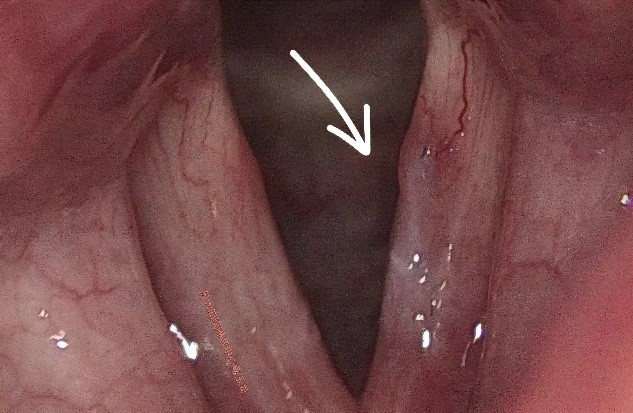

刘女士平时在上海工作生活,近2年来声音嘶哑逐渐加重,在外院就诊后诊断为“声带任克水肿”,专家建议手术。因为声带部位手术的特殊性,刘女士思考后决定审慎对待,要经过多方专家诊断结果一致后再做决定。在家人的推荐下,刘女士来到苏州大学附属第四医院嗓音专病门诊进一步就诊。在嗓音专病门诊,马玉龙副主任医师为刘女士做了动态频闪喉镜检查,发现左侧声带任克间隙水肿比较明显,严重影响声带黏膜波,导致声音嘶哑,发音费力。综合评估后建议声带显微外科手术治疗。